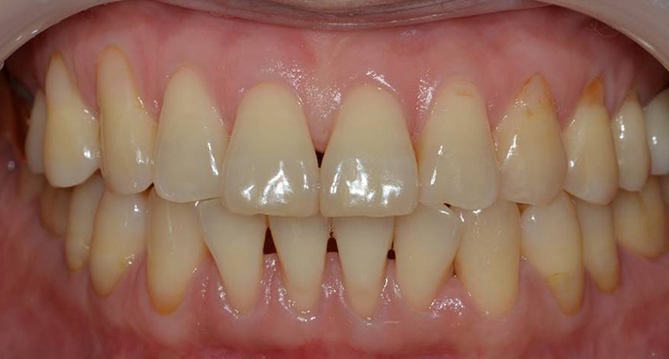

연세새빛치과 전체치아교정[클리피씨] 교정 전

연세새빛치과 전체치아교정[클리피씨] 교정 후